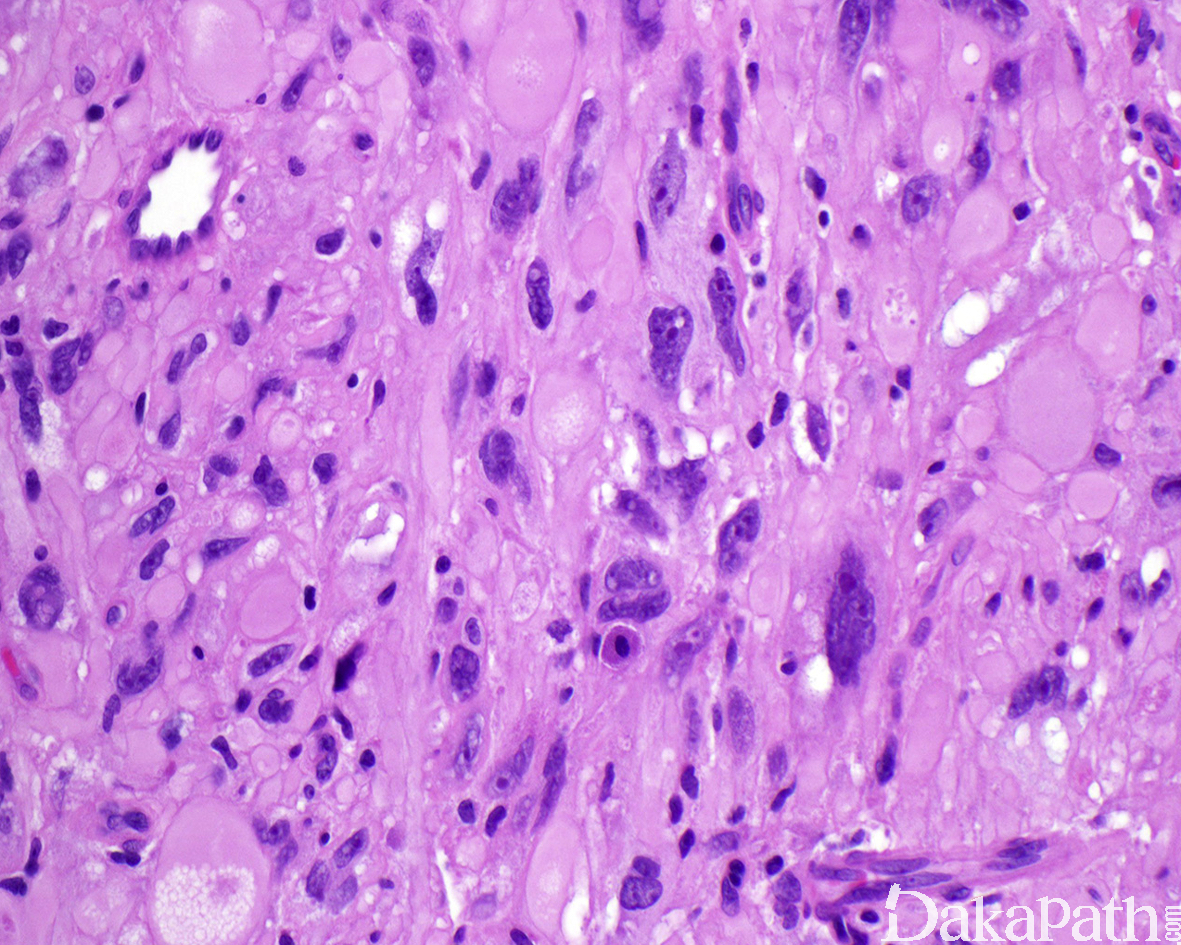

镜下肿瘤中等富于细胞,主体位于皮下组织内,偶见于真皮内;

总体上肿瘤呈膨胀性生长但伴有不同程度的周围脂肪浸润或真皮累及;

瘤细胞梭形至上皮样,呈束状或实性片状排列,胞浆丰富呈颗粒状、原纤维状或玻璃样改变,部分表现为黄瘤样胞浆;

大多数肿瘤细胞核具有明显的多形性,常见奇异性核或多叶核以及核内假包涵体,核染色质深伴 1 至 2 个明显的核仁;

尽管肿瘤富于细胞且伴有明显的非典型性核,但核分裂像非常罕见,大多数<1 个/50 高倍镜视野,无非典型核分裂像,无肿瘤性坏死;

间质内可见分支状薄壁的毛细血管以及散在的慢性炎细胞和肥大细胞浸润。